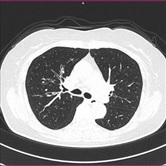

胸部CT画像 腹部CT画像

胸部 |

肺炎、肺がん、肺梗塞 |

咳、息苦しさ |